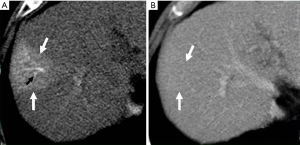

Because HCC remains amongst the most significant long-term sequelae of the cirrhotic liver, small HAPS when observed must carefully be distinguished from de novo HCC. The differentiation between HCC and HAPS is a critical clinical issue requiring a vigilant approach.

The major differentiating imaging features between HAPS and HCC are as follows: (I) a HAPS usually exhibits a peripheral location with a wedge-shaped appearance, straight margin, and cone-shape on three-dimensional reconstructed images. Normal vessels can be seen coursing through the area. (II) “Washout” is regarded as diagnostic for the differentiation of hypervascular HCC from non-tumorous HAPS. The equilibrium phase is also extremely useful in this differentiation as HCC usually arise as an area of heterogeneous low attenuation (or intensity), while the signal attenuation of a HAPS not arising with an HCC will not decrease below parenchymal background (Figure 16). (III) Repeat follow-up imaging procedures usually demonstrate the resolution or stability of a HAPS, as opposed to growth of an HCC.